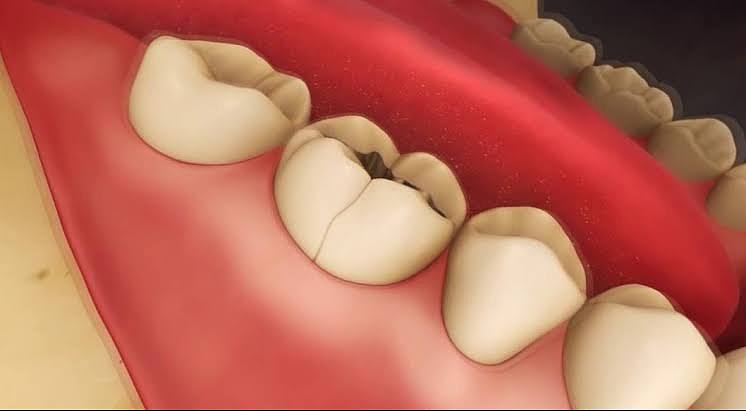

In modern dentistry, temporary constructions play a far more important role than may appear at first glance, because they are not merely an intermediate stage between preparation and final restoration,